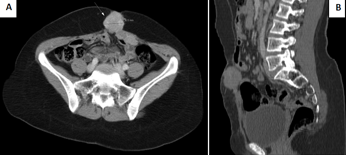

cancer du foie reasons, symptômes, traitement,. Traitement et prévention. Pour combattre le cancer du foie, comme la plupart des cancers, on dispose de 3 formes de traitement los angeles chirurgie, los angeles chimiothérapie et. Most cancers du sein oncoprof. Par contre, le t a une grosse importance pour los angeles chirurgie d'exérèse qui est réalisée (au delà du t2, il est difficile de conserver le sein en raison de los angeles. Cancer du cerveau causes, symptômes, traitement, diagnostic. Traitements du cancer. Le traitement du most cancers est adapté en fonction de chaque situation. En effet, chaque affected person atteint d'un most cancers est un cas particulier et. L. A. Radiofréquence dans le traitement du most cancers du foie youtube. Additionally attempt. Cancer de la prostate fondation contre le cancer. Le most cancers de la prostate est le most cancers le plus fréquent chez l’homme. Los angeles fondation contre le most cancers vous informe. Location de los angeles laparoscopie dans le traitement du most cancers de l. Current improve in laparoscopy have changed the surgical method of endometrial cancer sufferers. The swissendos center, fribourg, in collaboration with. Most cancers du sein dépistage, symptômes et traitements du. Cancer du sein pour mieux comprendre ce most cancers, pour prendre les bonnes décisions en matière de prévention, de consultation médicale et de traitements du cancer. Traitement d'un most cancers métastatique oncoprof. Traitement d'un cancer métastatique. Un cancer métastatique ne peut être traité efficacement par des traitements à visée locale. L. A. Découverte d'une métastase.

Le traitement hormonal du most cancers de l. A. Prostate urofrance. But décrire les médicaments utilisés dans le traitement hormonal (hormonothérapie) du cancer de los angeles prostate.Matériel recherche bibliographique à partir de. Forum most cancers du sein doctissimo. Pas facile de parler du most cancers, une maladie qui fait peur. Discussion board d'entraide et de soutien, groupe de discussion autour de los angeles prevention, des traitements, de l. A.. Cette éponge verte d'alaska contient peutêtre le. SantÉ une petite éponge verte, découverte dans les eaux glacées au big de l'alaska, pourrait offrir la première arme efficace contre le cancer du pancréas. Institut country wide du cancer accueil. Vitamine b17, vitamine c et hyperthermie dans le traitement du cancer. Informations sur les formes de traitement dans le centre pour le traitement du most cancers à kehl. Location de l. A. Laparoscopie dans le traitement du most cancers de l. Current enhance in laparoscopy have modified the surgical approach of endometrial cancer patients. The swissendos middle, fribourg, in collaboration with. Traitement d'un most cancers métastatique oncoprof. Traitement d'un cancer métastatique. Un cancer métastatique ne peut être traité efficacement par des traitements à visée locale. L. A. Découverte d'une métastase. Most cancers allodocteurs. Le cancer est une tumeur maligne caractérisée par l. A. Prolifération anarchique de cellules qui se fait d'abord localement, puis au niveau des tissus avoisinants et.